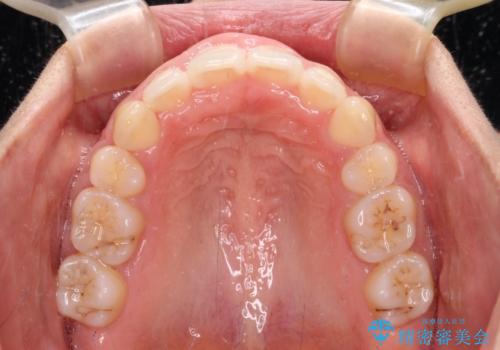

4本の歯を抜歯したことで、飛び出していた口元が引っ込み、横顔が大きく改善されました。

咬み合わせが悪化することのないようにスペースを閉じていくことができ、比較的スムーズに治療を進めることができました。